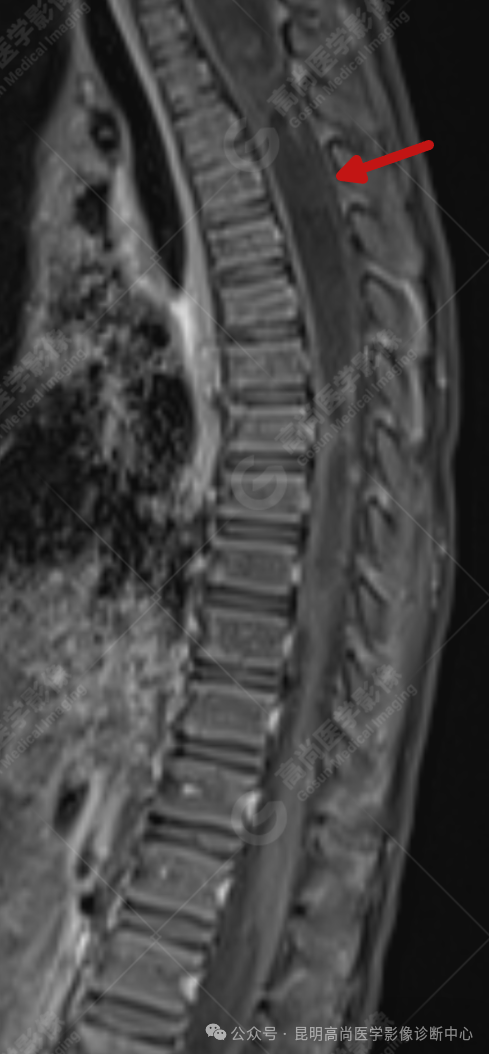

患者女,5 岁,出生时发现颈部包块,大小 3 cm×3 cm,5 年来无变化,拟行手术治疗,要求增强核磁协诊,否认体内金属物,无过敏史。

颈 3-5 层面颈后部软组织不规则片状异常信号影,脊膜膨出可能;颈 3、4 棘突局部显示不清;颈胸髓内(约颈 3-胸 9 椎体水平)异常信号影,考虑囊肿并局部颈髓空洞可能,肿瘤或其他待排;请结合临床及相关检查。